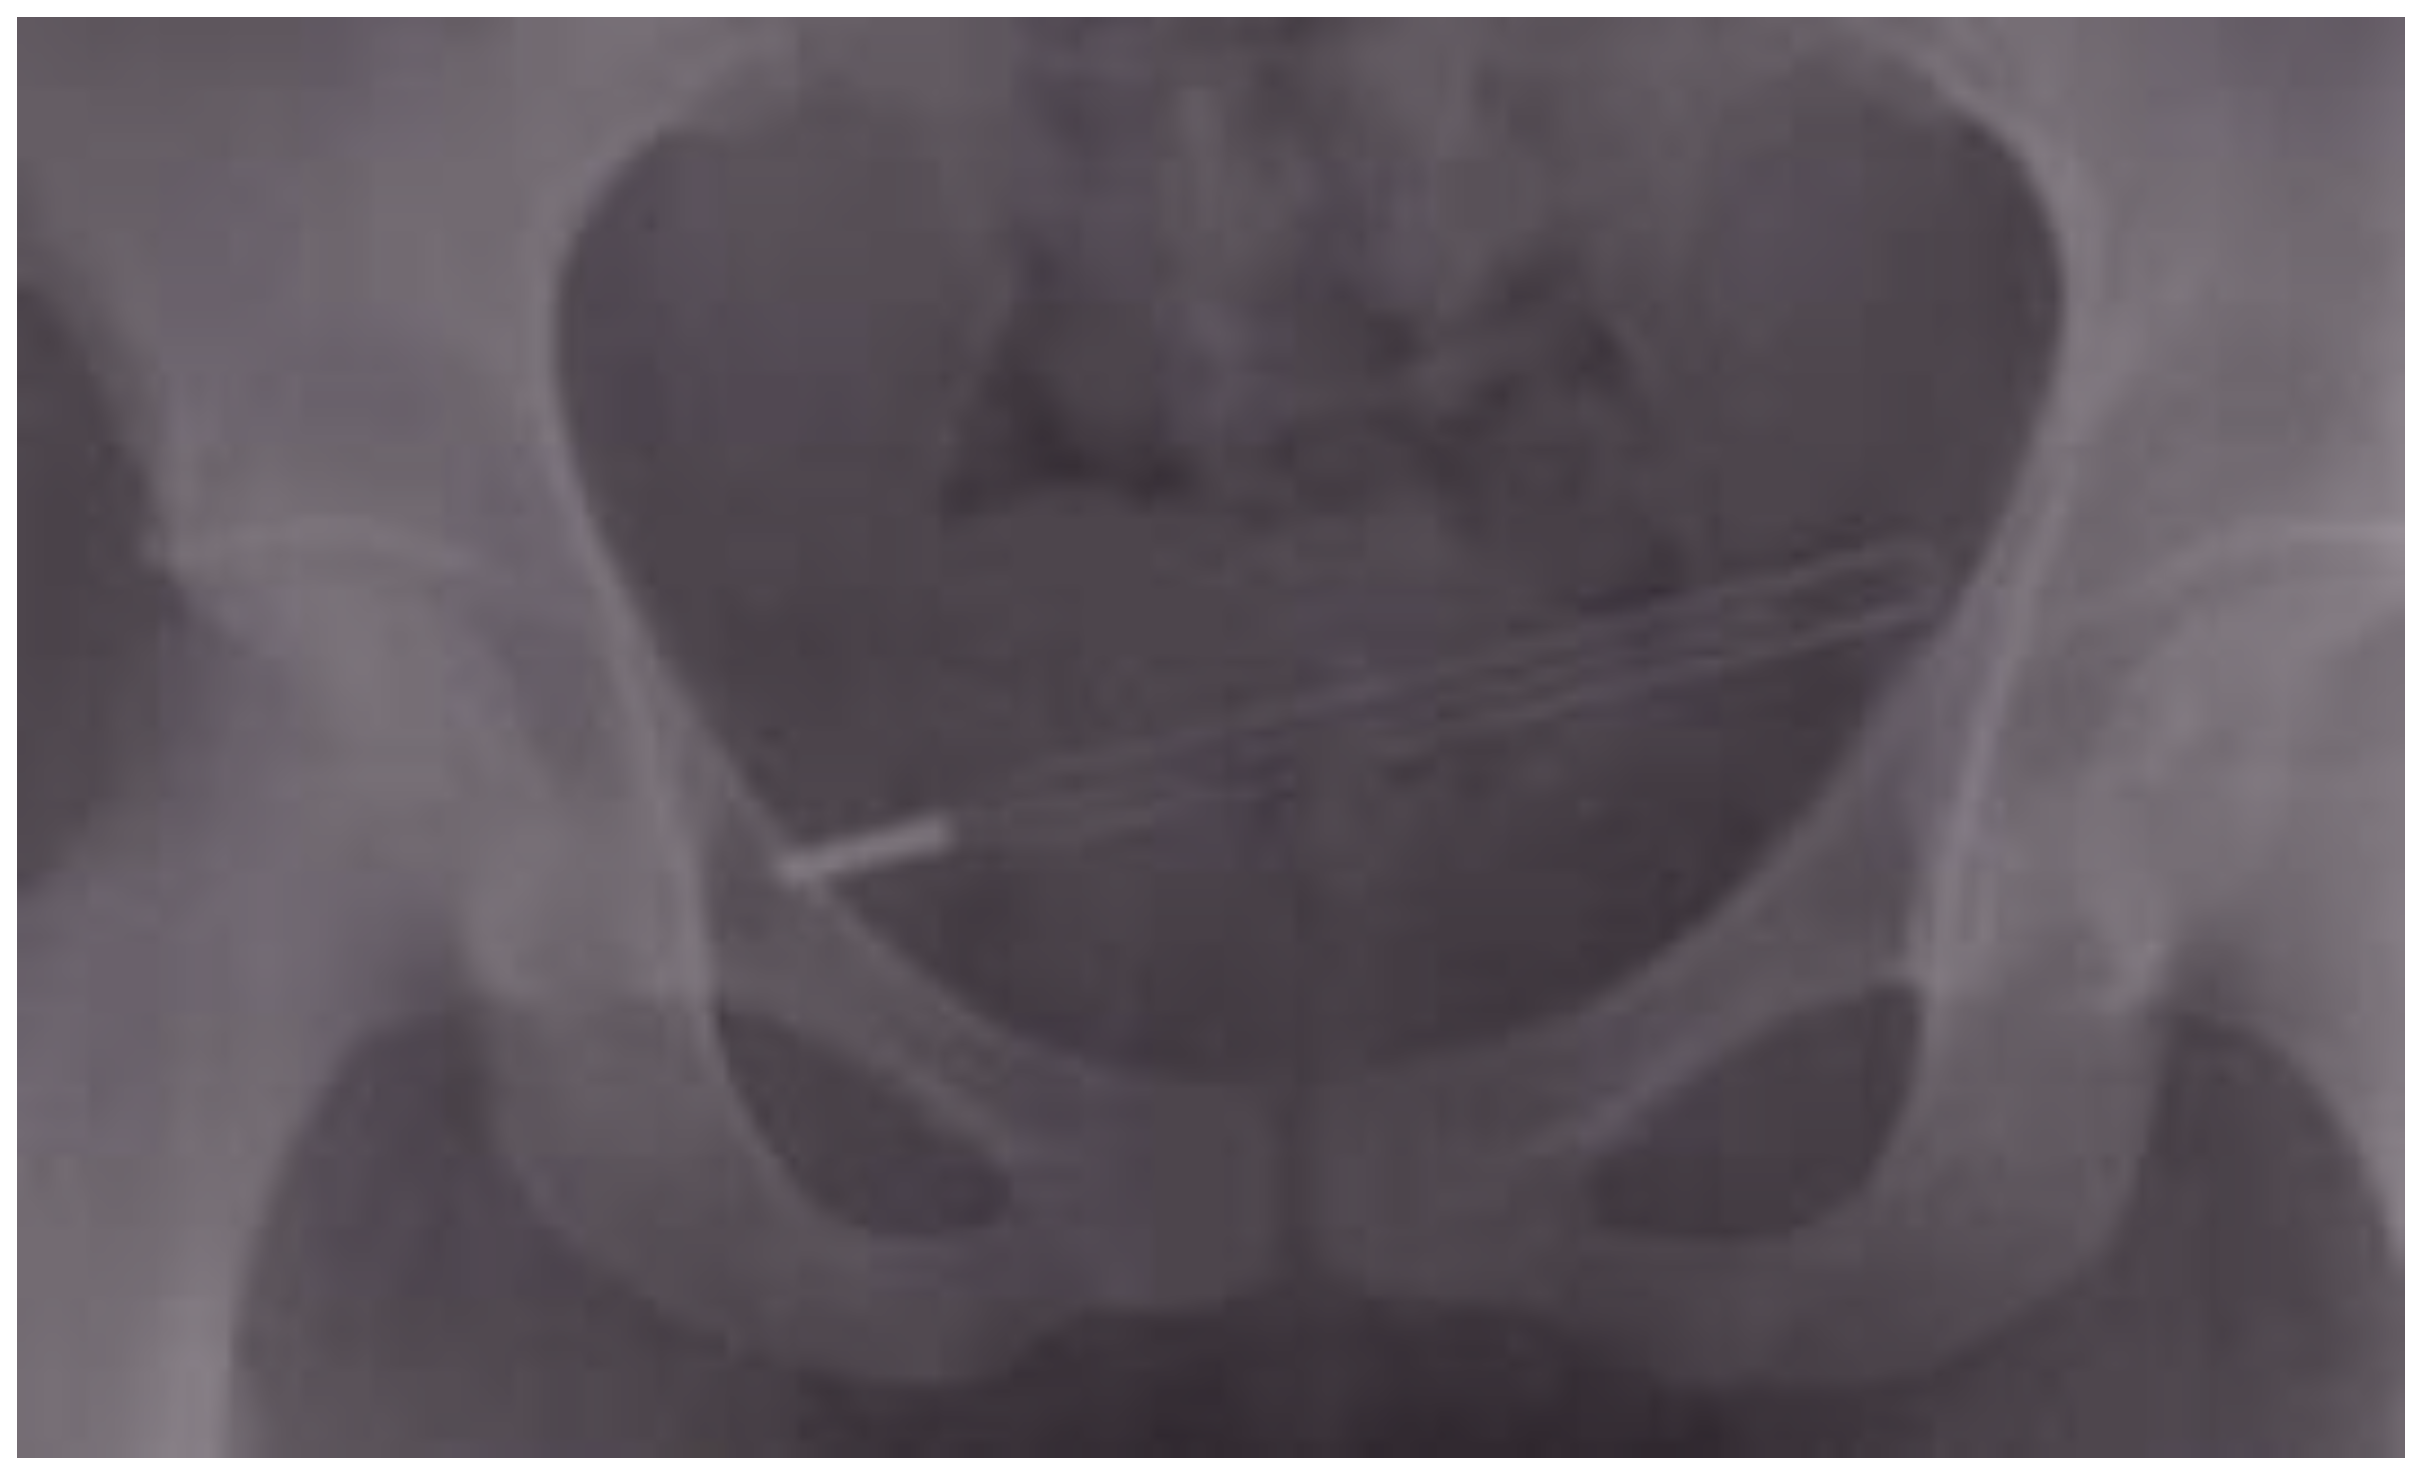

| 11 | 26 | M | silicone | urethra | alcohol intoxication | 1 week | abdominal pain, dysuria | cystoscopy |

| 12 | 51 | M | silicone | urethra | unknown | <24 h | AUR | cystoscopy |